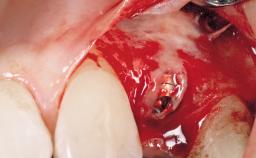

Late Placement of an Implant in a Maxillary Left Central Incisor Site

A 36-year-old female patient was referred for the replacement of the upper left central incisor (tooth 21), which had fractured. Although the tooth had been asymptomatic for many years, the crown began to loosen, at which time she presented to her dentist for an assessment. Teeth 21 and 22 had both been endodontically treated many years previously. She was a healthy individual and a non-smoker.

Soft Tissue Grafting Simultaneous

Soft Tissue Anatomy Intact Defective

Soft Tissue Contour and Volume Slightly compromised